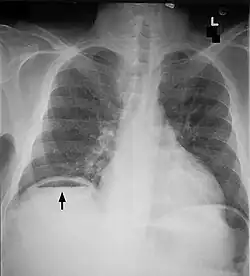

Medizin

In der Medizin bezeichnet eine Perforation den Durchbruch oder die Durchstoßung von Gewebe, welches eine Körperhöhle ummantelt.[7] Der Begriff wird dabei sehr vielfältig angewendet:

Krankheitsbedingte Perforationen kommen beispielsweise vor

- im Gastrointestinaltrakt: Speiseröhre, Magen, Zwölffingerdarm, Dünndarm, Dickdarm, Gallenwege

- im HNO-Bereich: Trommelfell, Nasenseptum

- in der Zahnmedizin

- in der Gynäkologie: Gebärmutter

- in der Urologie: Harnblase

- in der Augenheilkunde: Hornhaut

Eine Perforation der Speiseröhre ist immer lebensbedrohlich und kann durch einen Tumor ausgelöst werden. Geschwüre von Magen und Zwölffingerdarm können in die Bauchhöhle durchbrechen und ein akutes Abdomen auslösen. Auch Gallensteine können durch einen Druck auf die Gallenblasenwand eine Perforation bewirken. Eine Perforation des Dickdarms kommt zum Beispiel bei der Colitis ulcerosa vor. Im HNO-Bereich kann sich der Eiter einer Mittelohrentzündung durch eine Perforation des Trommelfells in den Gehörgang entleeren. Eine Perforation der Gebärmutter kann unter einer Spontangeburt nach einem Kaiserschnitt durch Ruptur der alten Narbe entstehen. Die Harnblase kann durch einen bösartigen Tumor perforiert werden, so dass sich der Urin in die Bauchhöhle entleert.